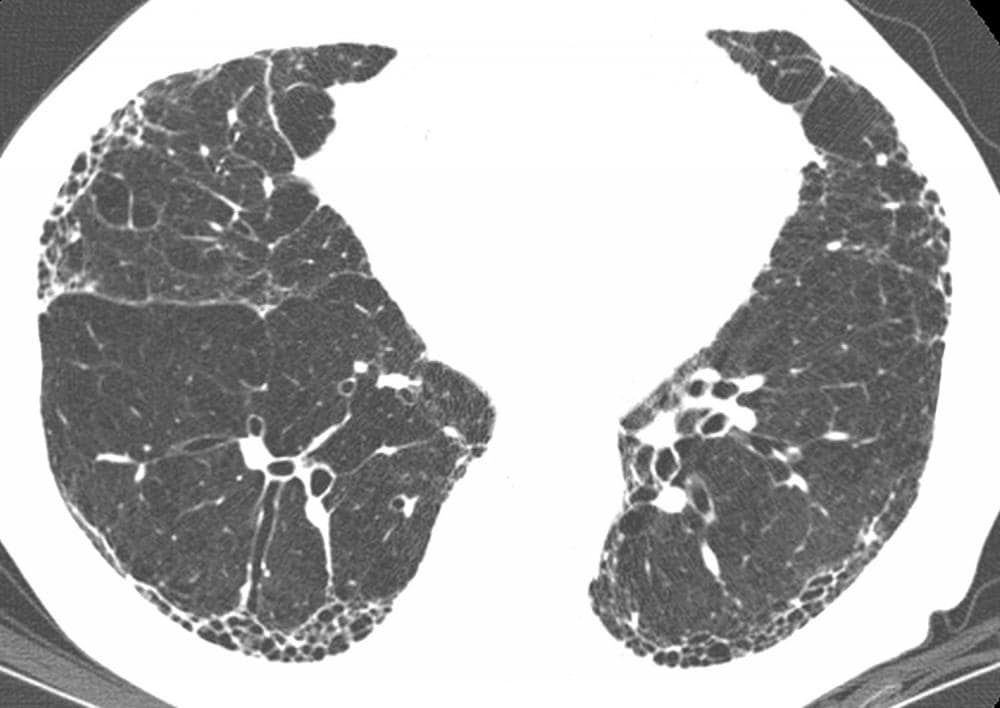

Фиброз легких и загар - фото презентация